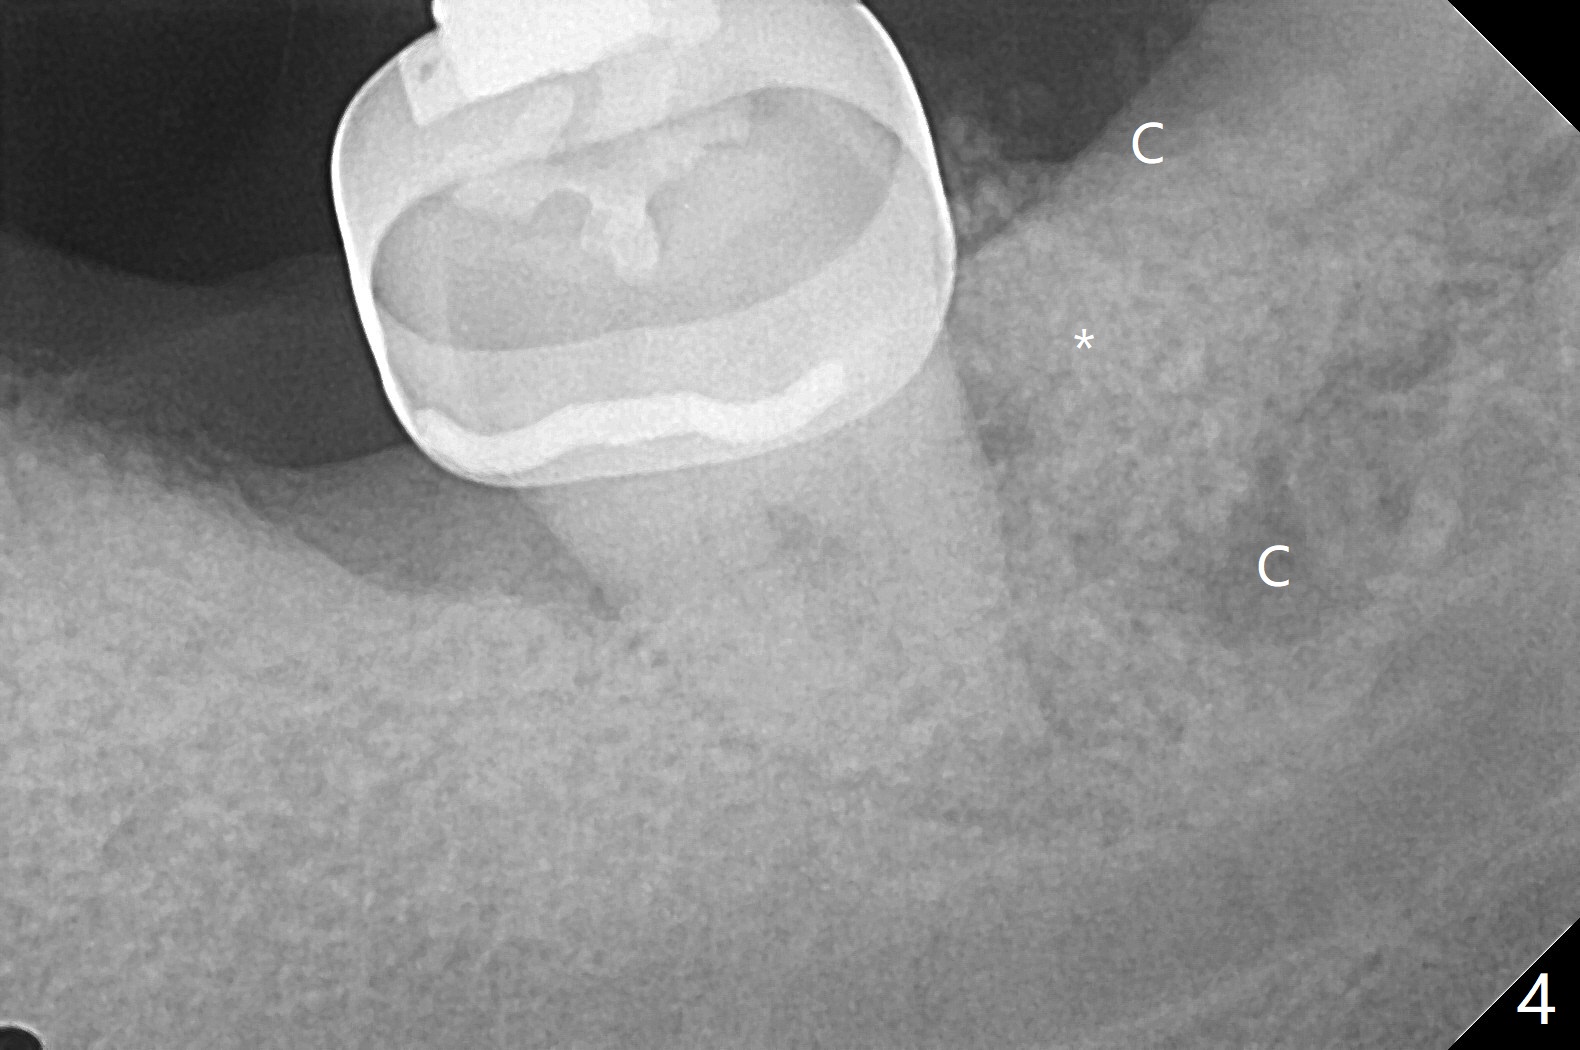

前几周介绍一个矫正砸锅病例,微型植体植入左上6(for intrusion,矫正压低)颊侧远中没有骨质区域,造成局部骨质缺损(图一:>)。颊侧,腭侧牙龈沟切口,翻瓣,清创后,植入粘性骨粉(图二:*,也在颊侧,腭侧植骨),覆盖PRF膜,使用4-0 Monoglyc缝线缝合。对于左下6缺失,原先病人(31岁女)要求前移7,8,初步矫正(2个月内)引起7松动(图三),经过讨论,病人同意拔除8,然后竖直7。拔出后,放置半块胶原塞(控制出血,图四:C),然后植骨(*),最后放置另外半块胶原塞(C),4-0 PGA缝合。术后一个月腭侧放置power chain压低磨牙(图五)。术后2.5个月缺牙间隙大于前磨牙,可以种植,同时7近中植骨(图六:*(粘性骨粉))。整合后利用6作为抛锚继续做7竖直。